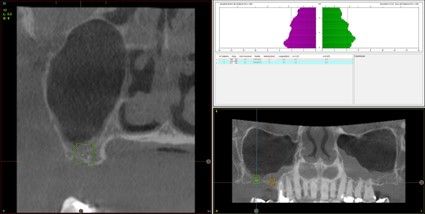

Resultados. Fueron reclutados 13 pacientes en los que se insertaron 30 implantes. Una vez insertados y cargados los implantes, la altura media final fue de 9,68 mm (+/- 2,66), lo que supone una ganancia promedio de 5 mm. A los 10 años, se observó una disminución media de la altura ósea ganada en los implantes en conjunto de 0, 29 mm (+/- 0,77). La media de la pérdida ósea mesial fue de 0,73 mm (+/- 0,75 mm) y la media de la pérdida ósea distal fue de 0,98 mm (+/- 1,2 mm). La supervivencia fue del 100%.

Results.Thirteen patients were recruited and 30 implants were inserted. Once the implants were inserted and loaded, the mean final height was 9.68 mm (+/- 2.66), which represents an average gain of 5 mm. At 10 years, there was a mean decrease in the overall bone height gain of the implants of 0.29 mm (+/- 0.77). The mean mesial bone loss was 0.73 mm (+/- 0.75 mm) and the mean distal bone loss was 0.98 mm (+/- 1.2 mm). Survival was 100%.

Los senos tratados con la técnica de elevación transcrestal sin material de relleno muestran un incremento de entre 2,5 mm12,13 hasta 4.4 mm14,15 en la altura ósea lograda sobre el ápice y una supervivencia de los implantes que se sitúa entre un 94 y un 100%16-17. En este trabajo se presenta un estudio retrospectivo donde se ha evaluado la inserción de implantes extracortos (5,5 y 6,5 mm) en zonas posteriores maxilares mediante la técnica de elevación de seno transcrestal con la fresa de ataque frontal sin la utilización de material de injerto, con un tiempo de seguimiento de 10 años para poder objetivar el comportamiento de los implantes a largo plazo y de la técnica empleada.